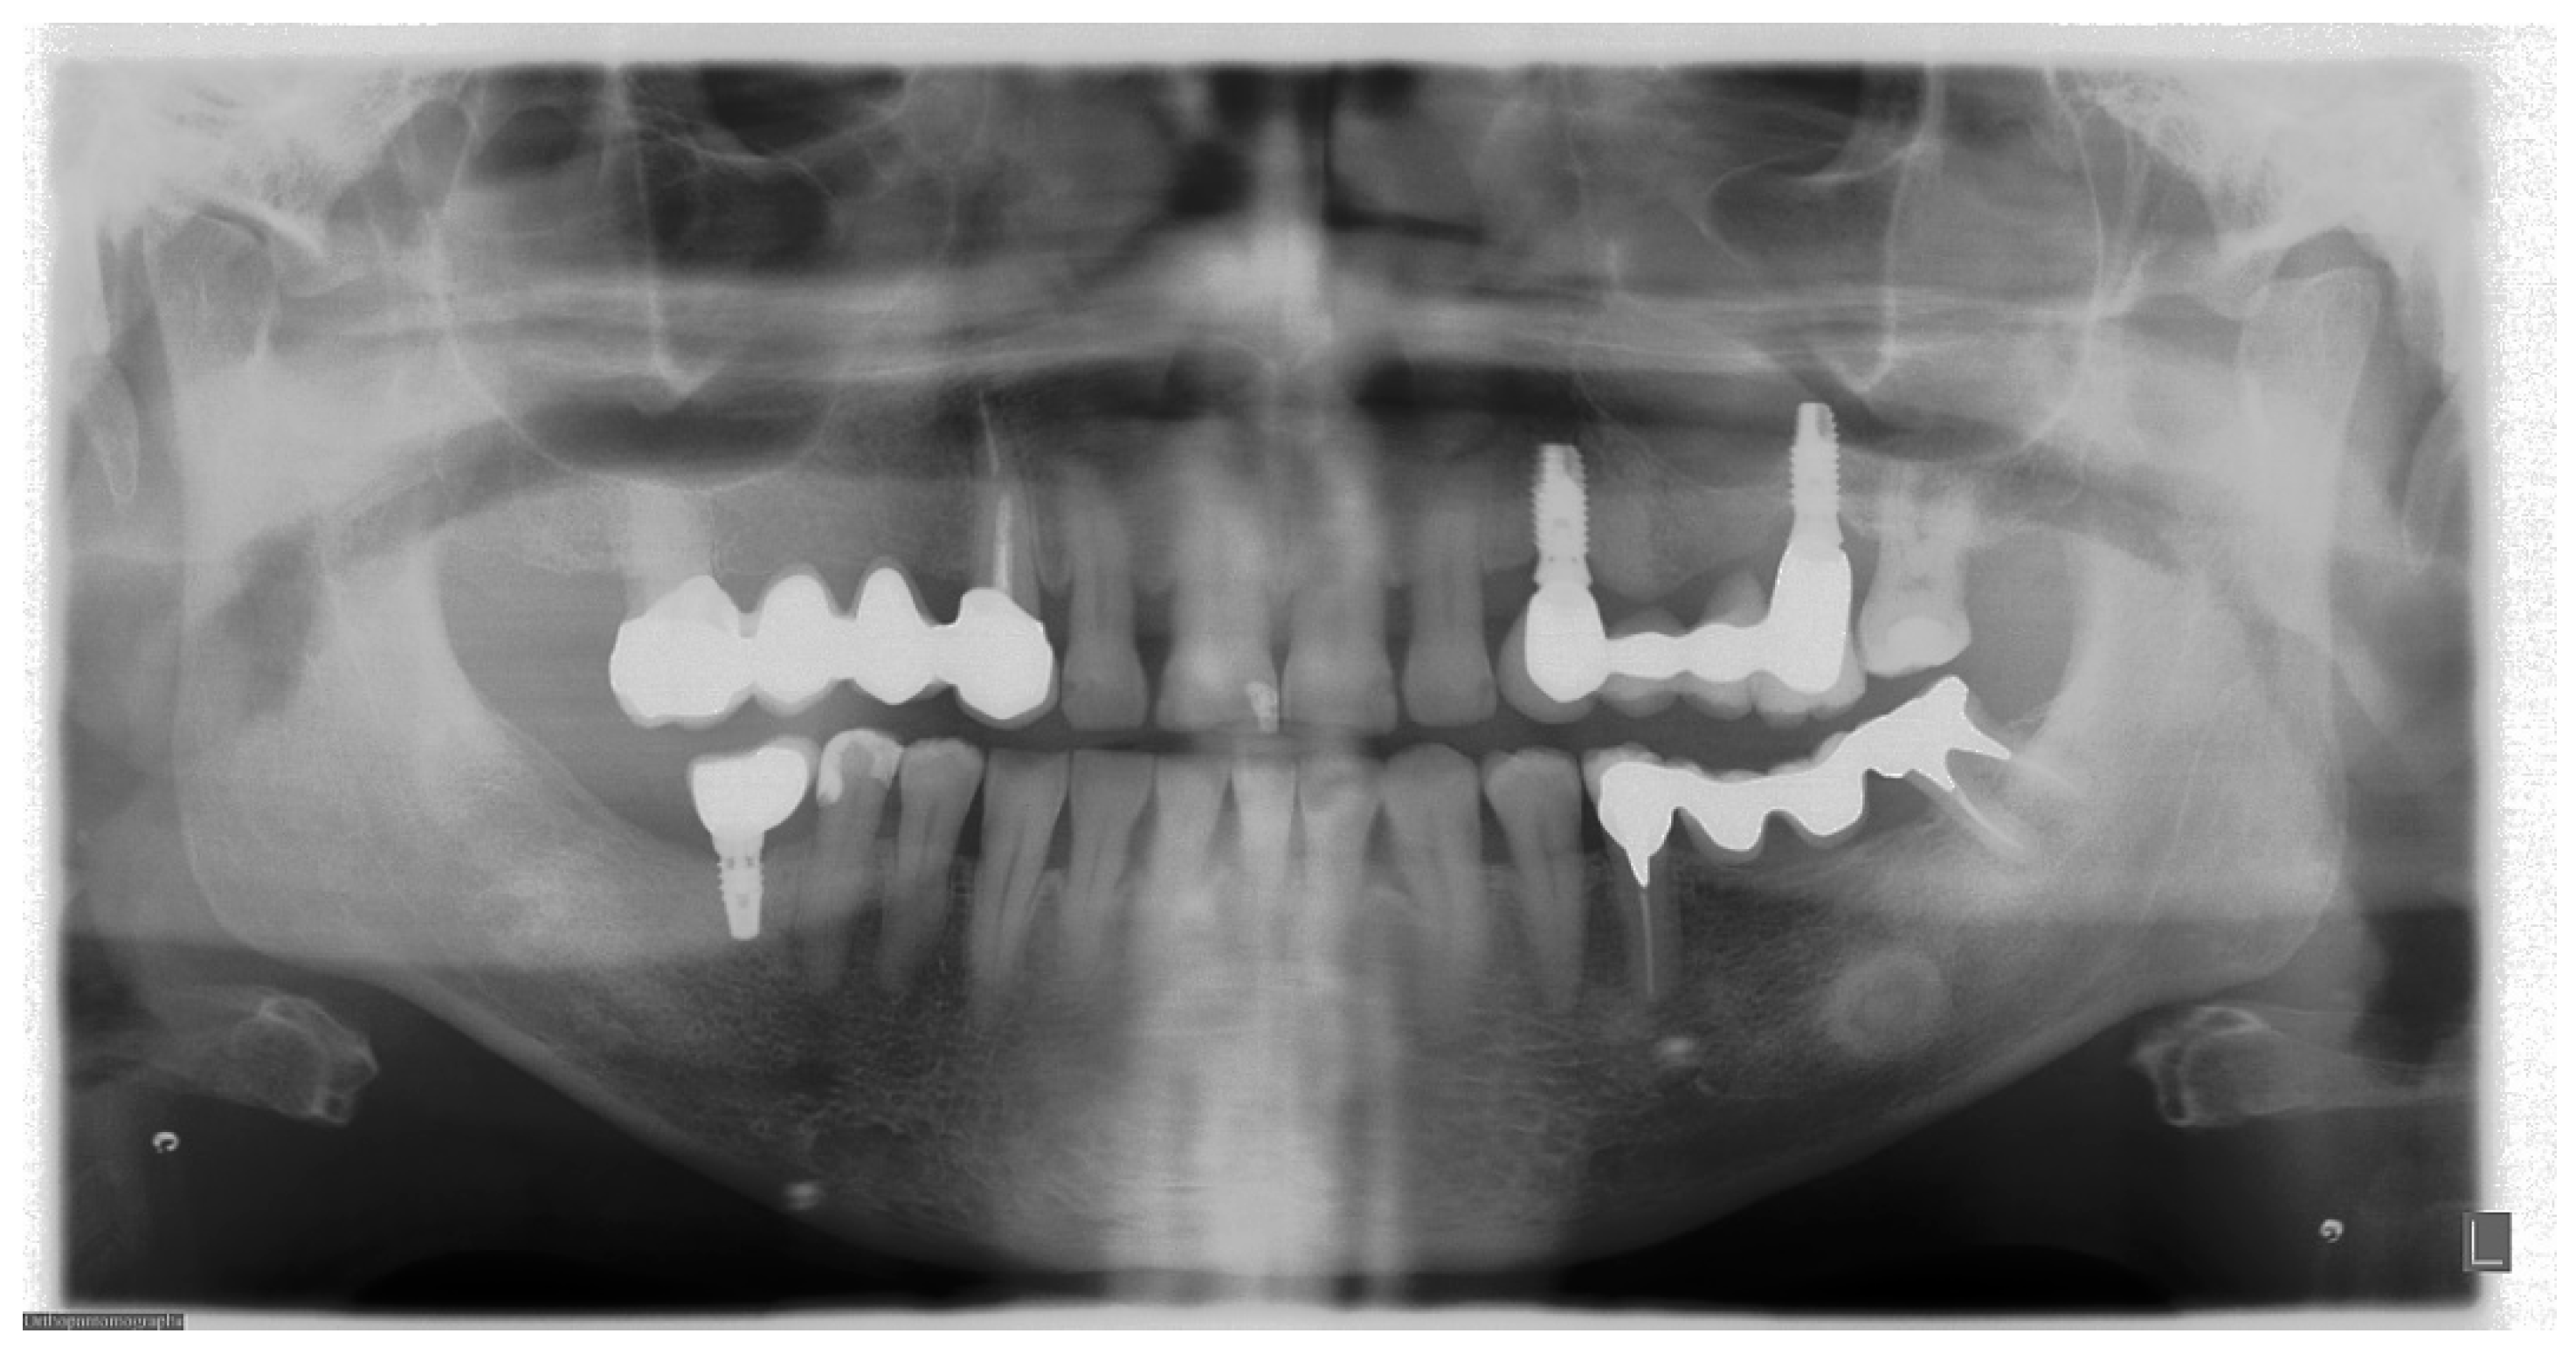

7. Metal and Motion Artefacts